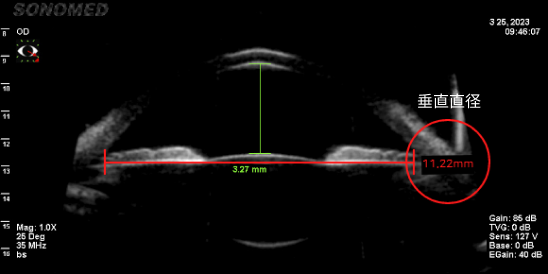

只有准确测量眼内空间是否足够,才能确定能否手术、晶体尺寸、可最小化晶体旋转概率的植入位置。

由于垂直直径平均比水平直径长,因此垂直型V-Toric ICL是在宽敞的空间内植入尺寸适中的晶体,晶体不接触周围组织,预防了晶体植入手术的副作用并提高了稳定性。

• 水平眼内空间测量(11.01mm)

• 垂直眼内空间测量(11.22mm)

垂直直径空间更广